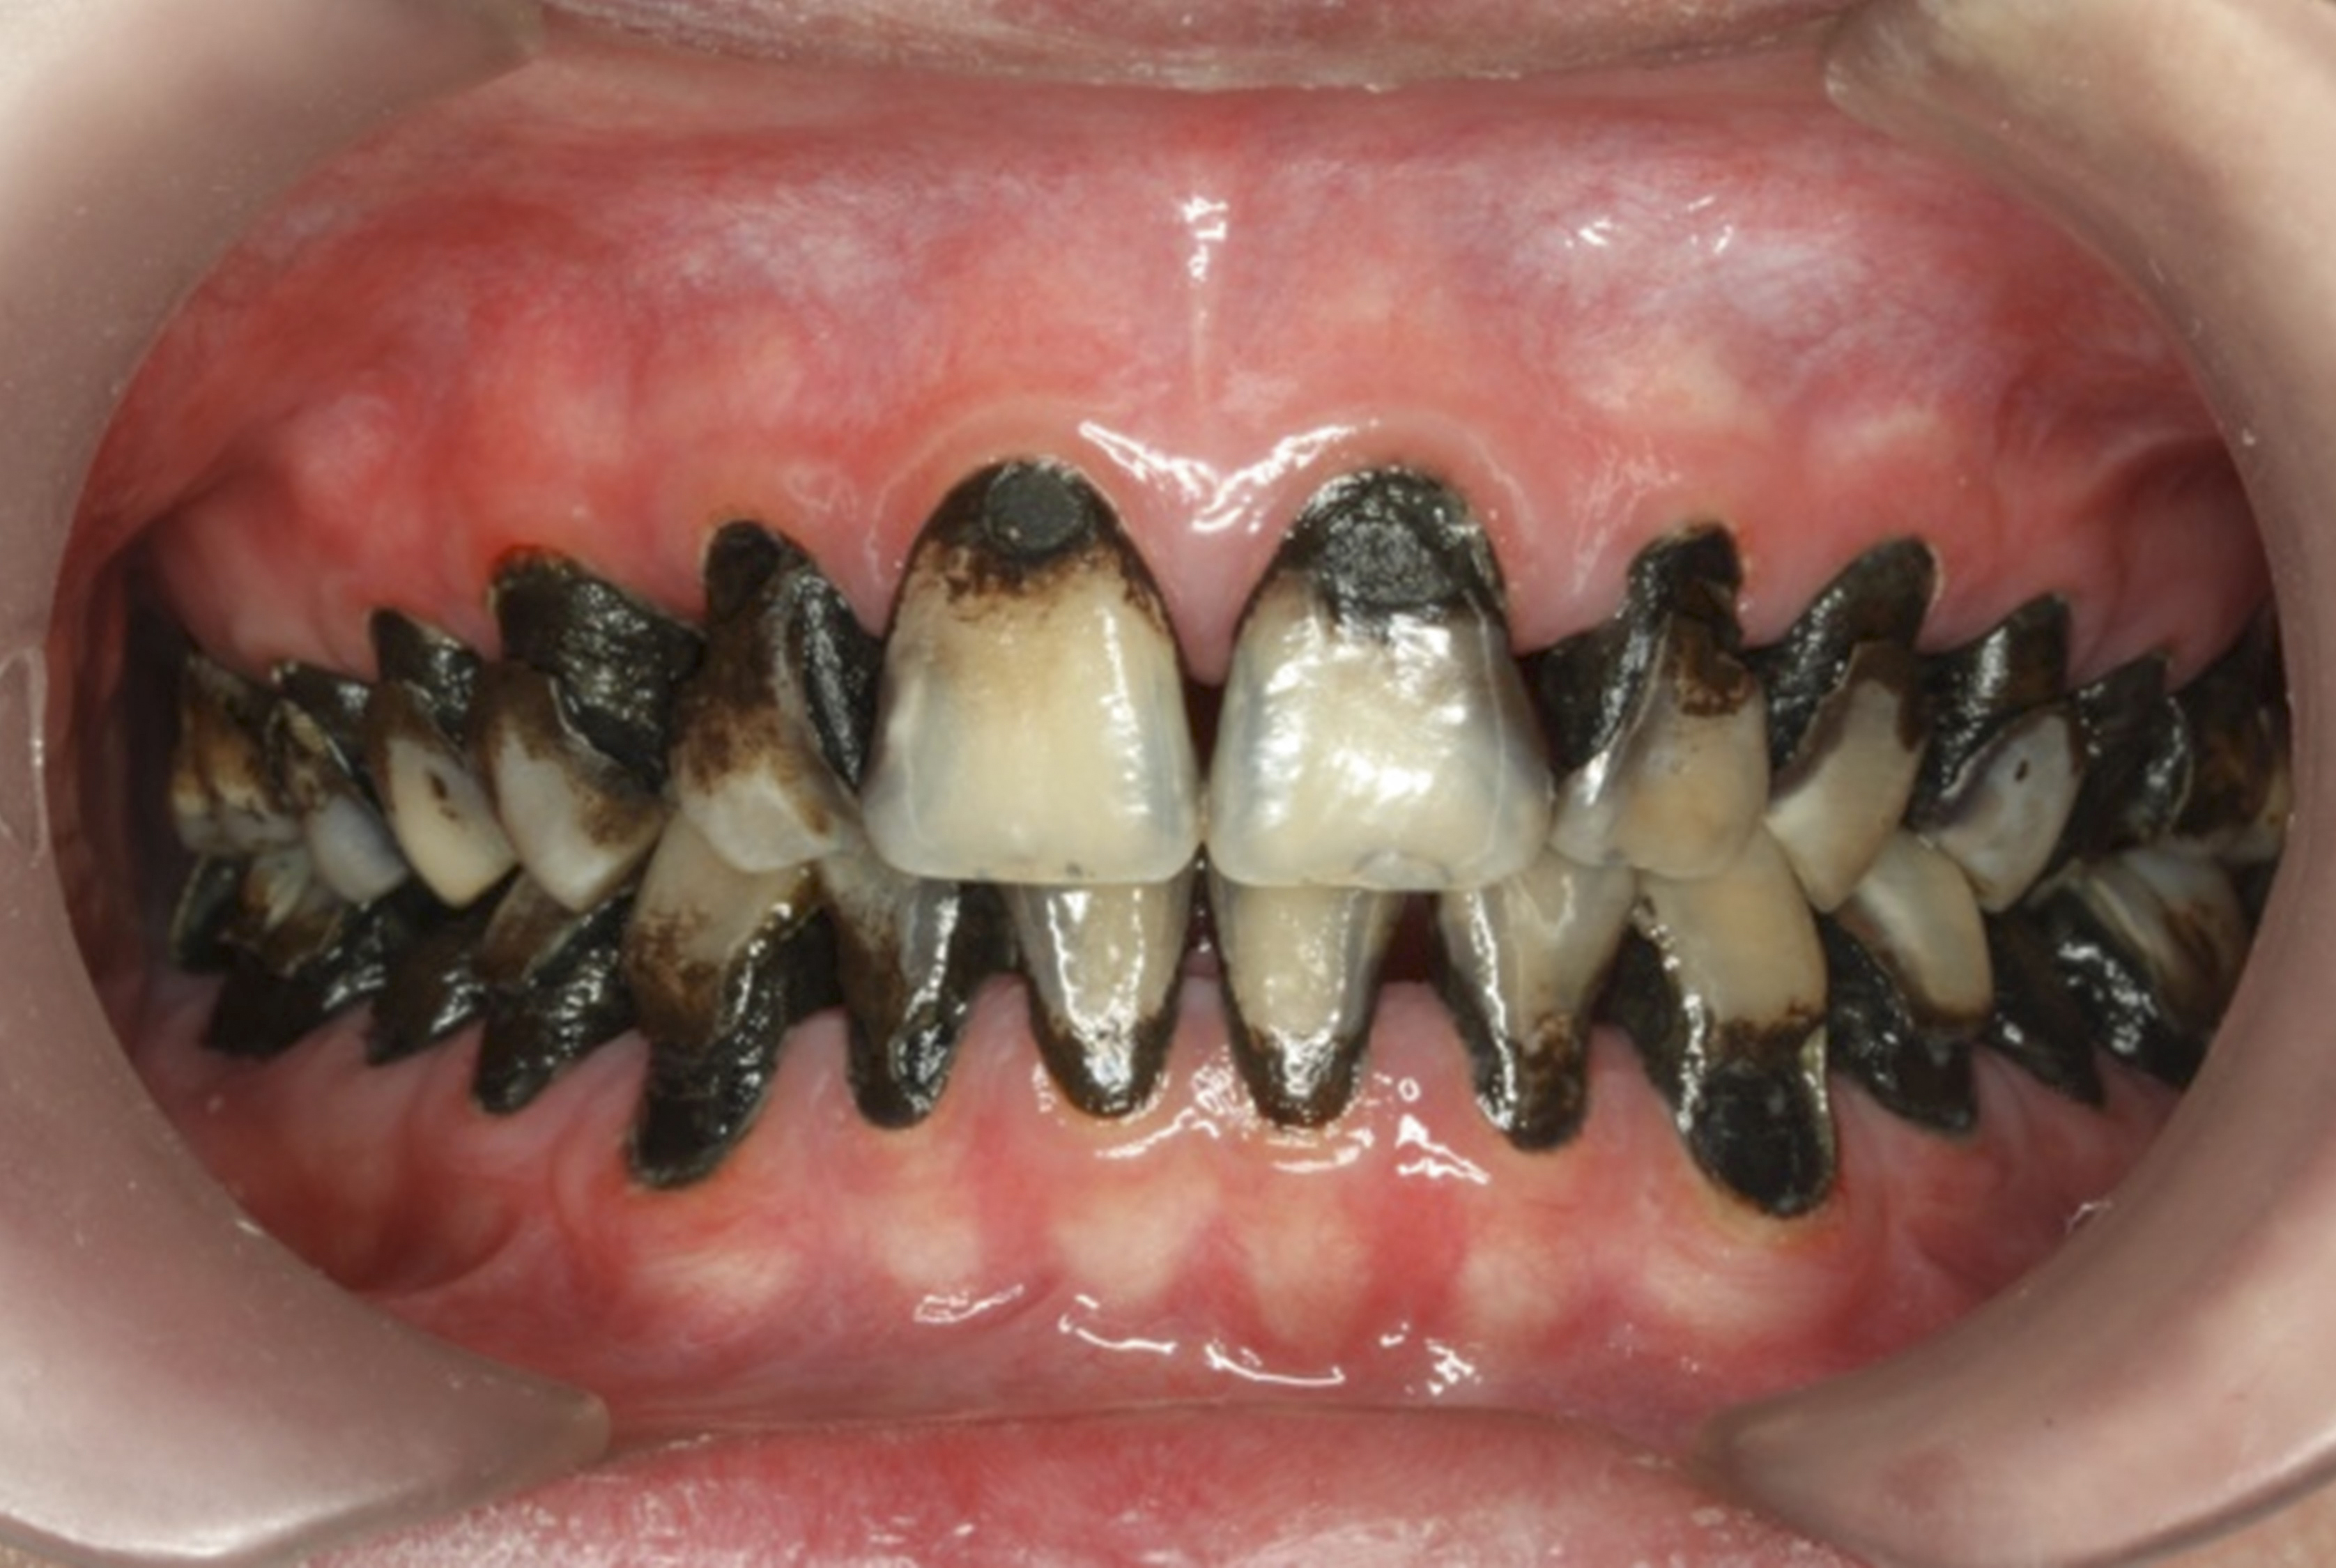

The inherent disadvantage of SDF is that the caries lesions will be stained black after SDF application. SDF stops caries progression by forming a hard, blackened, impermeable layer on the tooth surface that is resistant to caries (Figure 5 through Figure 9). The authors’ clinical observations are that the darker the color, the more likely the caries arrested. Some patients may not be pleased with the esthetics of this treatment outcome; therefore, it is important to inform the patients and parents (for child patients) about this treatment outcome. Moreover, SDF can stain clothes and the skin of the body. Though it does not cause any pain or damage, an SDF stain on skin cannot be easily washed away. It takes around 7 days for it to disappear, and the stain on clothes is permanent.22

There is no consensus on the frequency of application, and 38% SDF has been used annually or biannually on clinical trials in children23,31,33,34 and in elderly.30,35 Yee and his co-worker found one-off application of 12% SDF was ineffective in arresting caries in children.31 The present authors applied 38% SDF weekly for 3 weeks to speed up the process of caries arrest and for treatment of rampant caries.36 One of the present authors’ case reports demonstrated that three weekly applications of 38% SDF can arrest rampant caries and relieve pain from hypersensitivity on a teenager. The SDF-treated caries were found arrested, and they turned coal black in appearance (Figure 9).

Fig 8. Use of 38% SDF to arrest rampant caries in a young teenager. Fig 8: Pre-treatment intraoral frontal view of rampant caries. Fig 9: Frontal view of arrested caries after consecutive application of SDF for 3 weeks. (images from Chu, et al, 201436 [reprinted with approval])

Fig 9. Use of 38% SDF to arrest rampant caries in a young teenager. Fig 8: Pre-treatment intraoral frontal view of rampant caries. Fig 9: Frontal view of arrested caries after consecutive application of SDF for 3 weeks. (images from Chu, et al, 201436 [reprinted with approval])